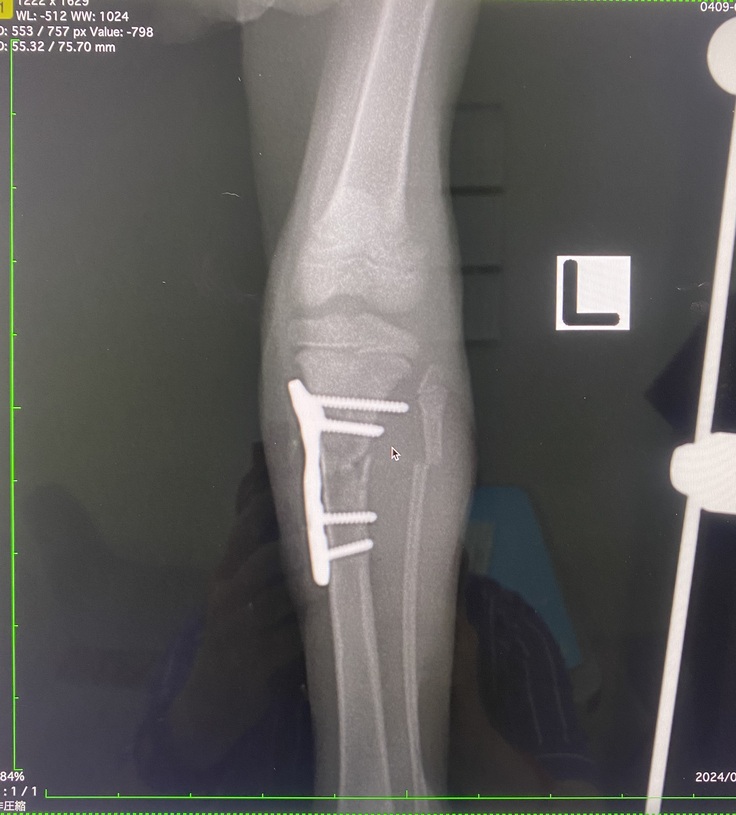

【7月17日左足下肢の手術】

左下肢は脛骨骨折と腓骨の不完全骨折で脛骨は上腕と同じくプレートでの固定をしました。腓骨は細いため自然に癒合するのを待つことになりました。